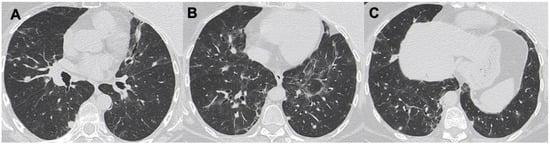

3.1. Consolidations

3.2. Nodules and Masses

3.3. Ground-Glass Opacities